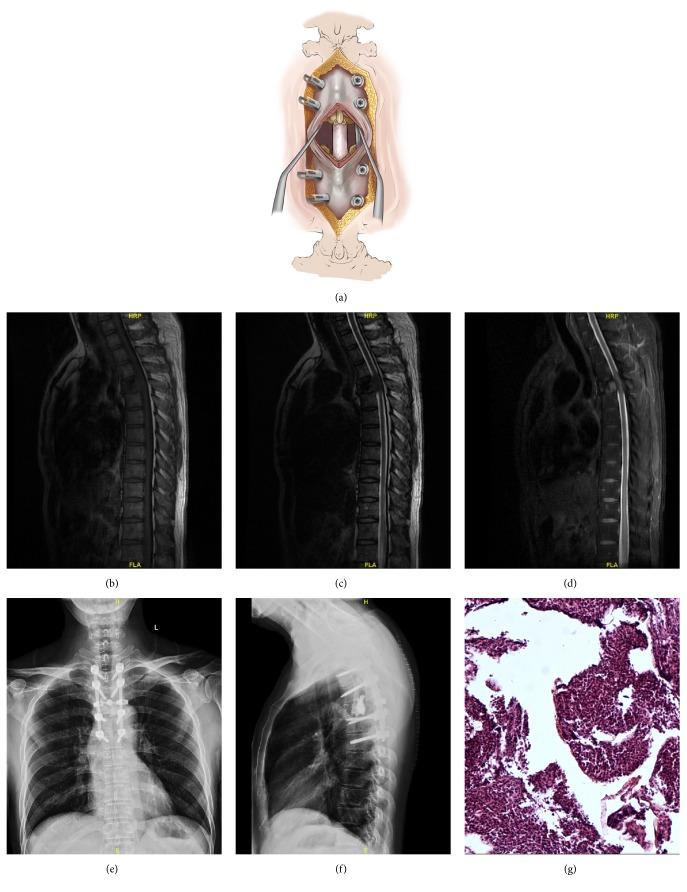

Patients with metastatic epidural spinal cord compression (MESCC) often need surgical intervention due to pain, neurological deficits, and spinal instability. Spinal disease is commonly treated via the minimally invasive mini-open approach. However, few studies have evaluated MESCC treatment via mini-open approach. The present study compared the traditional open approach versus the mini-open approach for thoracolumbar MESCC. A cohort of 209 consecutive patients who were diagnosed with thoracolumbar metastases and underwent corpectomy and polymethylmethacrylate reconstruction from 2010 to 2016 was retrospectively identified. Traditional open surgery was performed in 113 patients (open group; mean age 57.7 years), while 96 patients underwent mini-open surgery (mini-open group; mean age 54.3 years). Patients were followed up for 24 months or until death. The baseline characteristics of both groups were similar. The most common origin of the primary lesion was the lung (37.3%), hematological system (22.0%), and kidney (15.8%). Surgery effectively achieved pain relief, restored neurological function, and improved quality of life in both groups. The mini-open group was superior to the open group regarding estimated blood loss, blood transfusion, hospital stay, complications, and pain score. While the mini-open group had a longer operation time than the open group, the two groups had similar improvements in the Frankel grade and Karnofsky functional score. The 30-day mortality rate tended to be higher in the open group (5.3%) than the mini-open group (2.1%) without significance. The 24-month survival rate was similar in both groups (26.5% versus 26.0%). In conclusion, surgery improved pain, function, and quality of life in patients with MESCC. The mini-open approach resulted in less estimated blood loos, less blood transfusion, and shorter hospitalization than the traditional open approach, while both methods had similar mortality and morbidity rates. Thus, the mini-open approach may be more beneficial than the traditional approach for MESCC.

转移性硬膜外脊髓压迫症(MESCC)患者常因疼痛、神经功能缺损和脊柱不稳定而需要手术干预。脊柱疾病通常通过微创小切口开放手术进行治疗。然而,很少有研究评估过小切口开放手术治疗MESCC的效果。本研究比较了传统开放手术与小切口开放手术治疗胸腰椎MESCC的疗效。回顾性纳入了2010年至2016年间连续209例被诊断为胸腰椎转移瘤并接受椎体次全切除及聚甲基丙烯酸甲酯重建术的患者。113例患者接受传统开放手术(开放组;平均年龄57.7岁),96例患者接受小切口开放手术(小切口开放组;平均年龄54.3岁)。对患者进行了24个月的随访或直至死亡。两组的基线特征相似。原发病变最常见的起源是肺(37.3%)、血液系统(22.0%)和肾(15.8%)。手术在两组中均有效缓解了疼痛、恢复了神经功能并改善了生活质量。小切口开放组在估计失血量、输血、住院时间、并发症和疼痛评分方面优于开放组。虽然小切口开放组的手术时间比开放组长,但两组在Frankel分级和卡氏功能评分方面的改善相似。开放组的30天死亡率(5.3%)倾向于高于小切口开放组(2.1%),但无统计学意义。两组的24个月生存率相似(26.5%对26.0%)。总之,手术改善了MESCC患者的疼痛、功能和生活质量。与传统开放手术相比,小切口开放手术导致的估计失血量更少、输血更少且住院时间更短,而两种方法的死亡率和发病率相似。因此,对于MESCC,小切口开放手术可能比传统手术更有益。